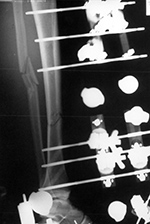

| Uniplanar external fixator with Steinman pins |

| The unilateral pins just penetrate the far cortex and are connected with radiolucent rod. The fixator is immobilizing a tibial fracture. From Benjamin, 1994 |